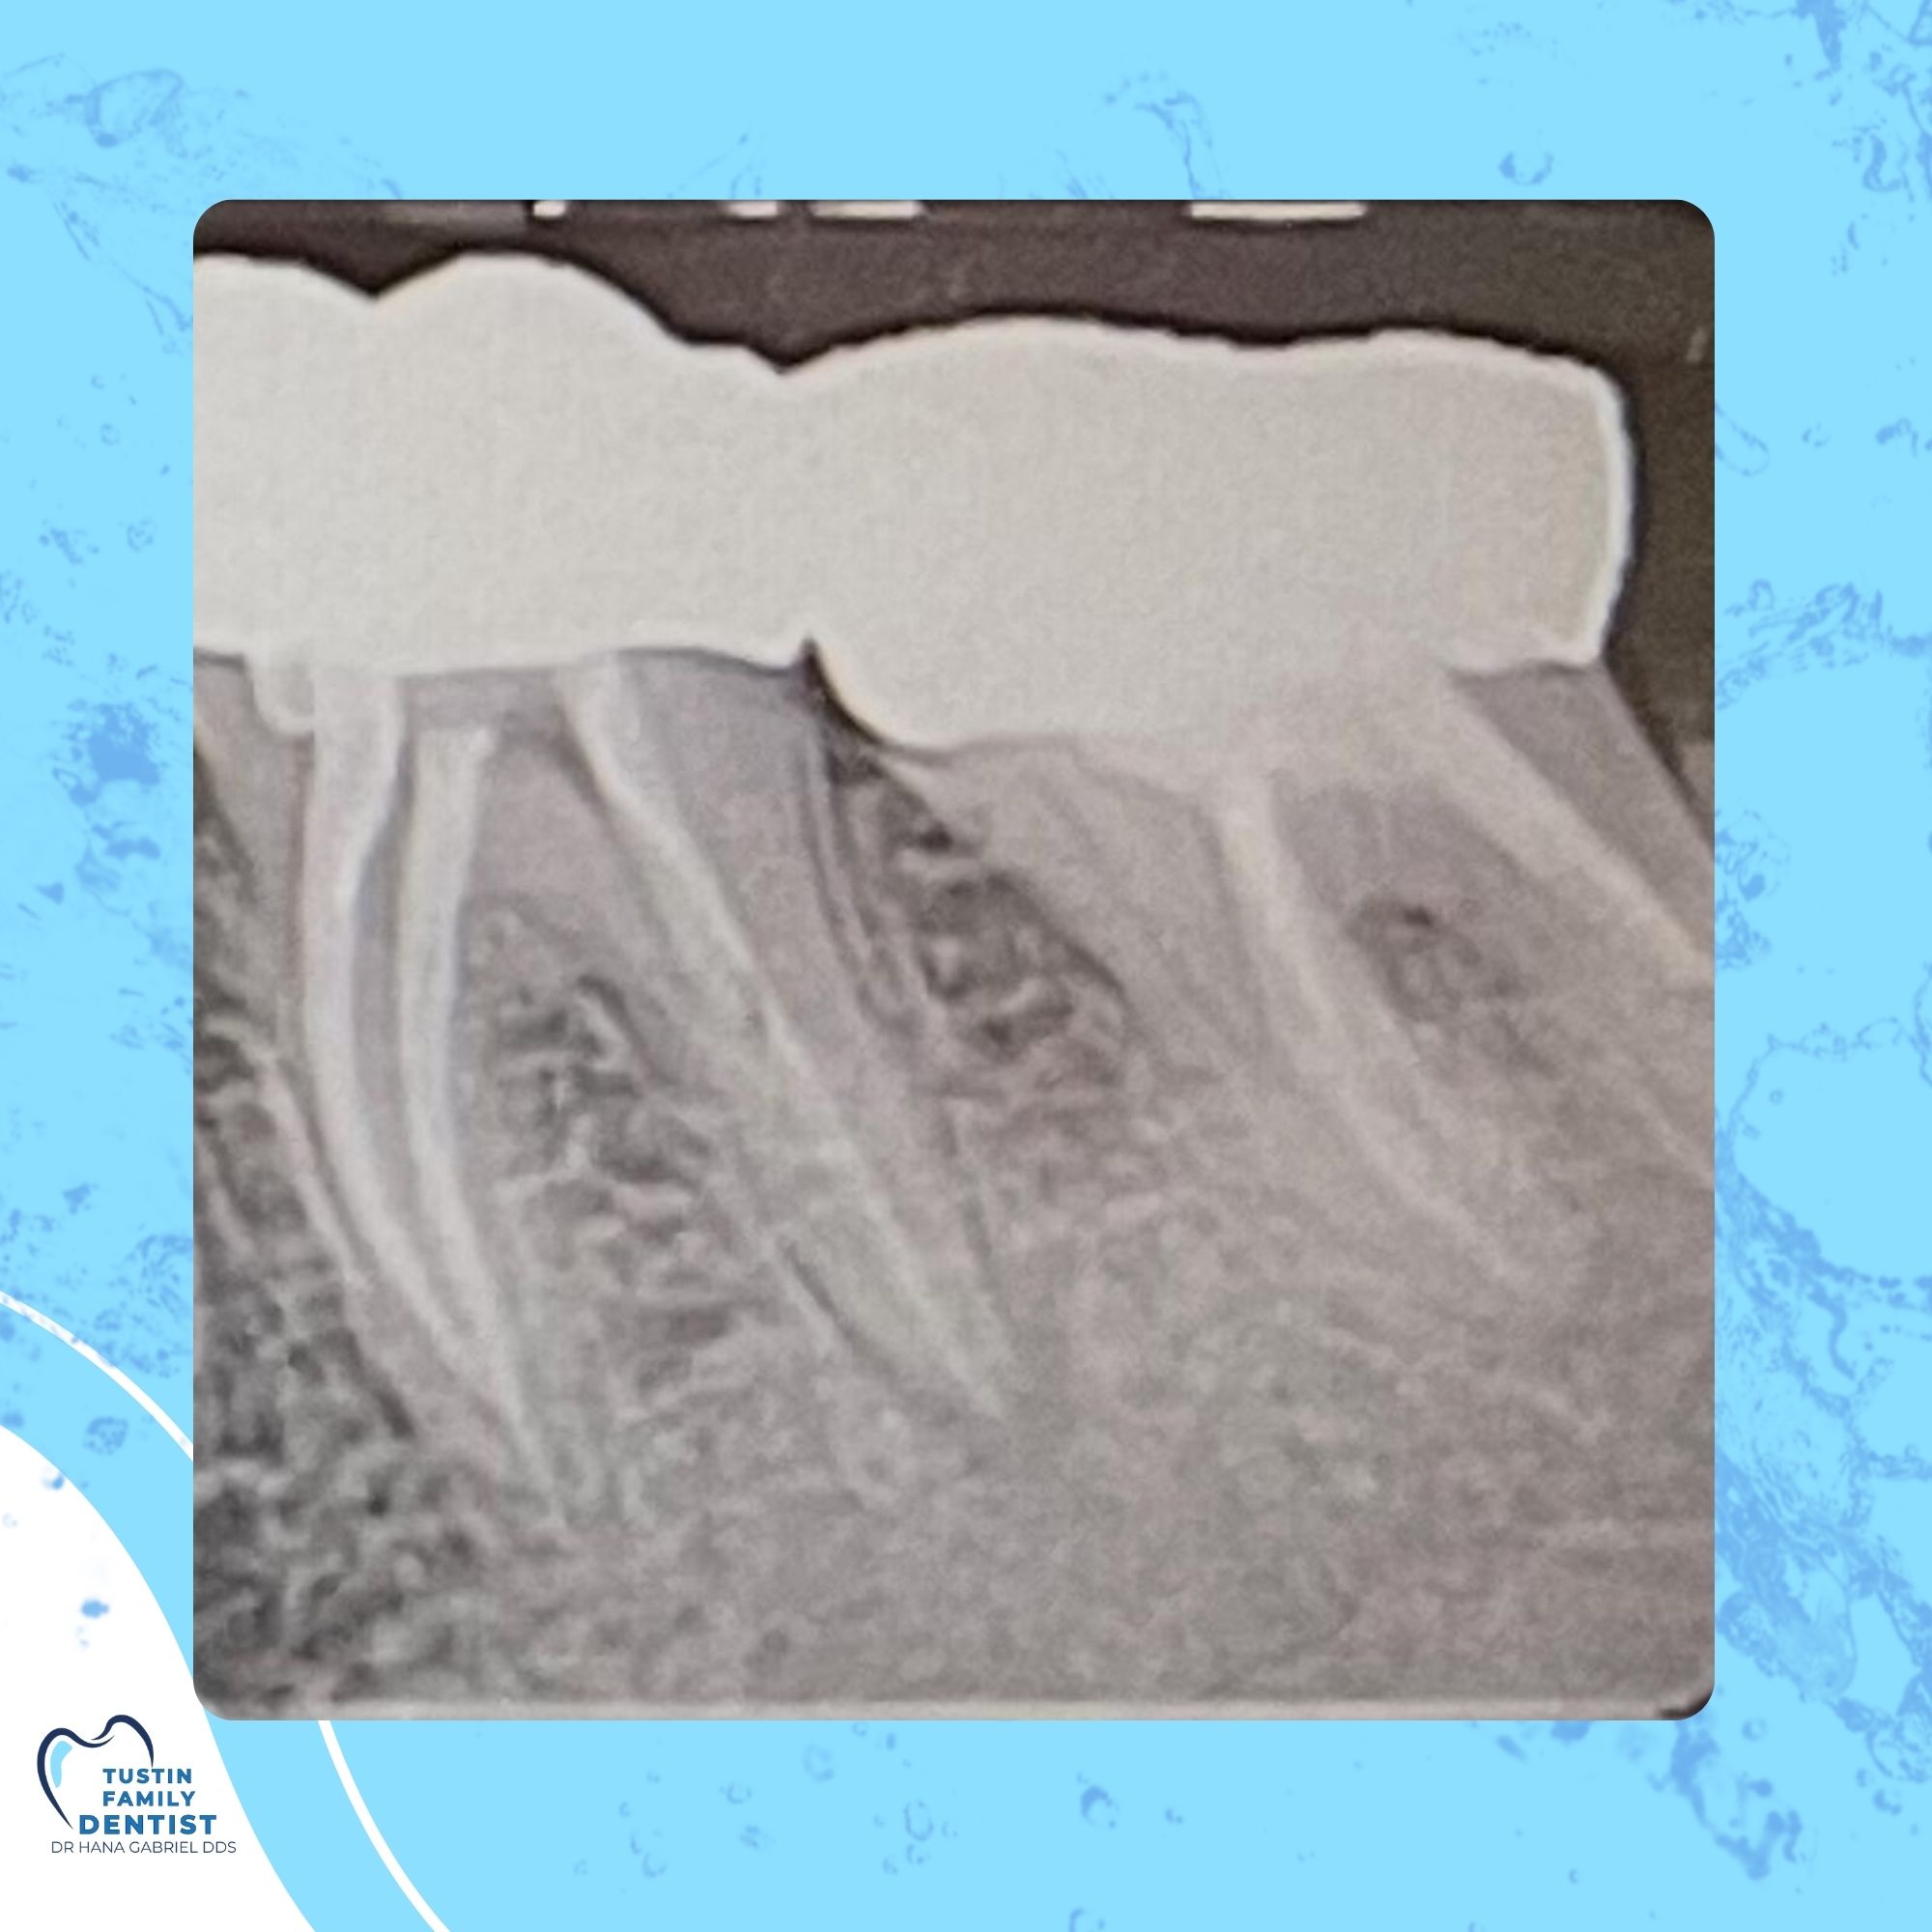

After numbing the area, we gently remove infected pulp tissue, disinfect the canal, and fill it with a biocompatible material. A crown or filling seals the tooth to restore its strength.